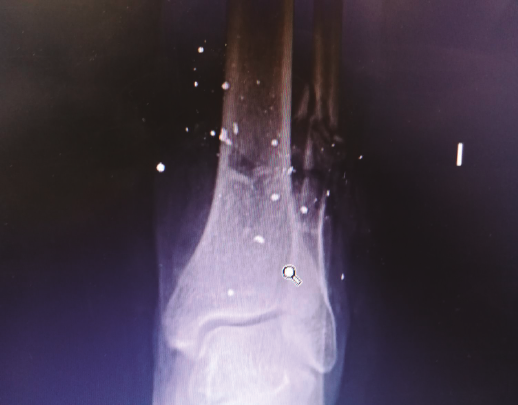

Figura 2. Radiografía tomada en urgencias. Se aprecia fractura del tercio distal del peroné con conminución ósea.

Se trata de un paciente varón de 49 años que presentaba una fractura abierta de peroné de tipo IIIB de Gustilo y Anderson tras sufrir un accidente por arma de fuego. Se observa defecto cutáneo de unos 10 cm en la región posterior de la pierna izquierda (Figuras 1A y 1B). En la radiografía se aprecia una fractura del tercio distal del peroné sin afectar a más estructuras óseas (Figura 2).